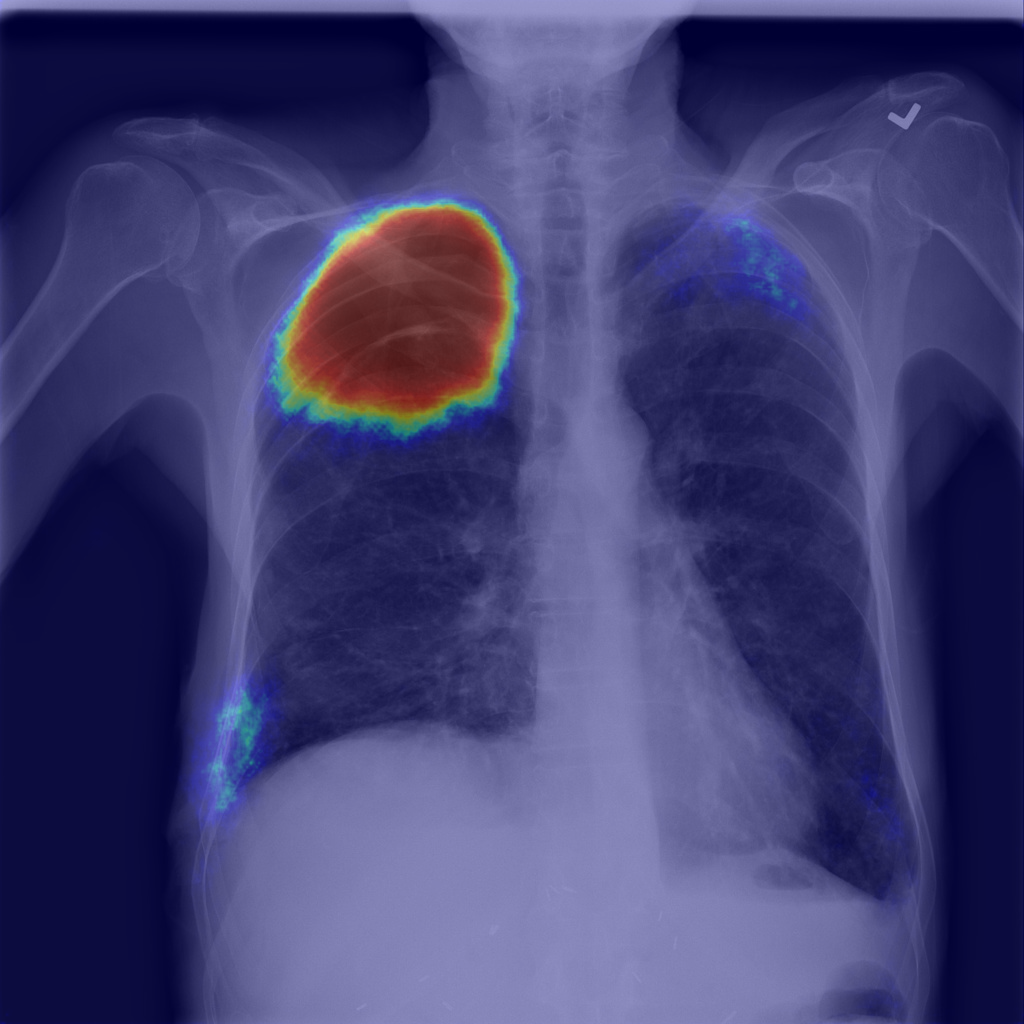

Refer to caption

(a) Image

(b) Step1.CAM

(c) Step2.IRNet

(d) Step3.Segm

(e) Mask

Figure 1: Pneumothorax localization maps for (a) a random image from the test set at each consecutive step of our method: (b) map after CAM extraction, (c) improved map by IRNet trained on the outcomed of step 1, (d) prediction of U-Net trained on step 2 results, all compared to (e) ground truth mask.